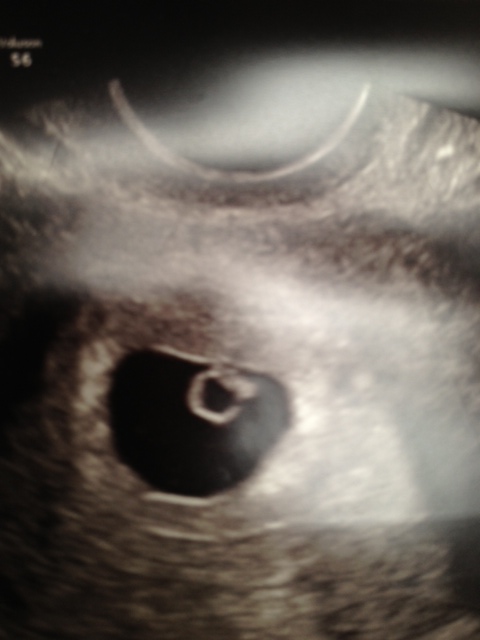

Does anyone know how to read the early predictions with the sac/placenta placement?

boy or girl ???? thanks!